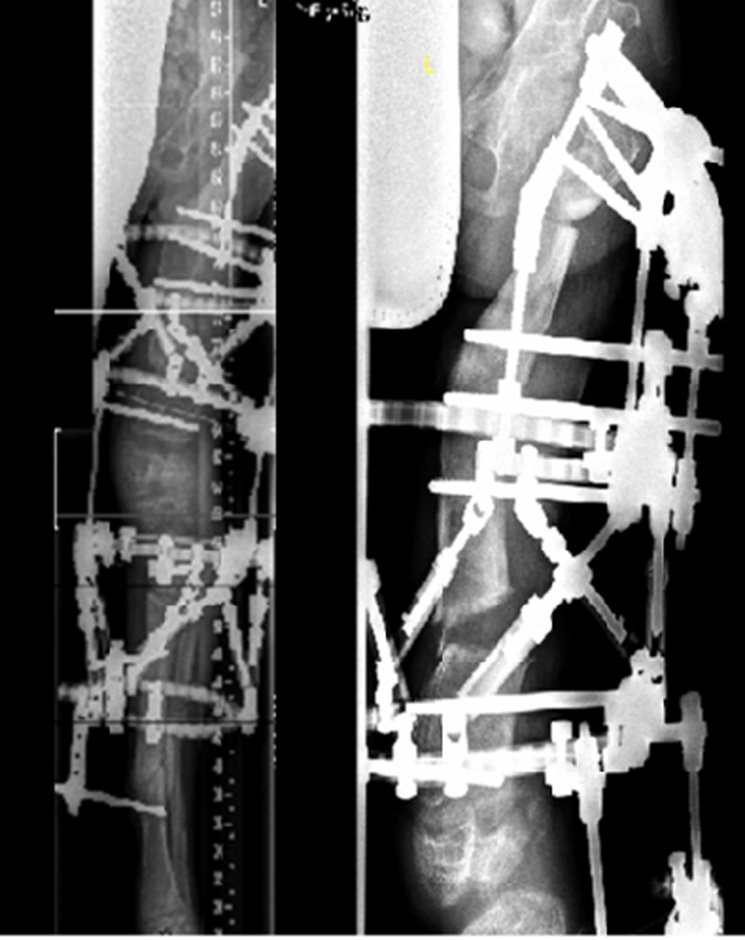

Figure 3

After performing a proximal and distal femoral osteotomy and a proximal tibial osteotomy on the left side, a Taylor Spatial Frame™ was mounted.

Figure 4

Three months later, the deformity of the left side was fully corrected by gradual distraction.